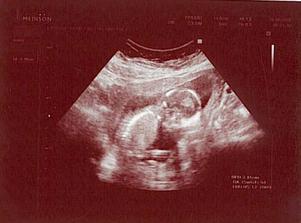

... 19.8. 3D .. byl to krásný zážitek .. máme natočeno 30-ti minutové DVD a dvě fotečky ... Viktorek potvrzen 🙂))))

... 21.8. kontrola ... Viktorek se má čile k světu, ukázal nám celé chodidlo, bylo to úchvatné